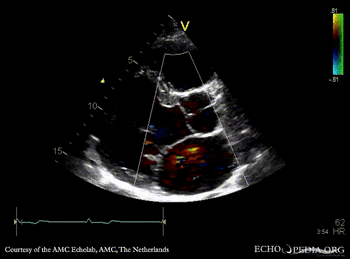

| PLAX with Color Doppler: mild mitral regurgitation